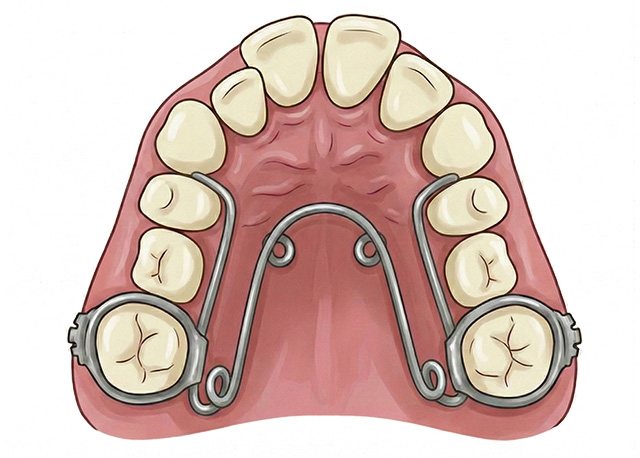

歯並び、かみ合わせ、骨格の状態を細かくチェックし、お子さんに合わせた装置を用いて矯正治療を行います。小児矯正の矯正装置には、大きく分けて「可撤式矯正装置(取り外し式装置)」、「固定式矯正装置」、「顎外固定装置」があります。

総入れ歯のような床(しょう:顎に密着する部分)を固定源にして、少しずつ歯を動かしたり顎を拡大したりすることで、歯並びやかみ合わせを整えていきます。装置中央にあるネジを回すことによって顎の横幅が広がります。歯の生え変わりの時期は、土台の顎の骨を拡大しやすく、将来の歯のでこぼこも予防できる可能性が高い装置です。

固定式矯正装置は、お子さんの意思にかかわらず常に装着されていますので、可撤式矯正装置(取り外し式矯正装置)と比べて効果が出やすい特徴があります。

歯列の横幅を広げる装置で、可撤式矯正装置の床拡大装置と役割は同じです。